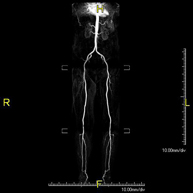

Prueba diagnóstica no invasiva que consiste en el estudio vascular del sector aorto-ilíaco y de los vasos arteriales de ambas extremidades inferiores, obteniendo imágenes de alta definición anatómica mediante el empleo de un campo electromagnético y ondas de radio (con un emisor y un receptor). Es indispensable el uso de contraste paramagnético (Gadolinio). Sin embargo, no utiliza radiación ionizante. La calidad de las imágenes permite realizar reconstrucciones en 2D y 3D. Está especialmente indicado en aquellos pacientes en los que hay sospecha de enfermedad vascular de ambas extremidades, en pacientes con enfermedad vascular de ambas extremidades como el mapa vascular antes del tratamiento (percutáneo o quirúrgico), como el mapa vascular pre-quirúrgico en pacientes con lesiones óseas o musculares que requieran cirugía, etc. - Angio-RM Arterias renales

Prueba diagnóstica no invasiva que consiste en el estudio de la arteria aorta abdominal, obteniendo imágenes de alta definición anatómica mediante el empleo de un campo electromagnético y ondas de radio (con un emisor y un receptor). Es indispensable el uso de contraste intravenoso paramagnético (gadolinio). Sin embargo, no utiliza radiación ionizante. La calidad de las imágenes permite realizar reconstrucciones en 2D y 3D. Está especialmente indicado en aquellos pacientes en los que hay sospecha de enfermedad vascular de ambas extremidades, en pacientes con enfermedad vascular de ambas extremidades como mapa vascular antes del tratamiento (percutáneo o quirúrgico), como mapa vascular pre-quirúrgico en pacientes con lesiones óseas o musculares que requieran cirugía… - Soft tissue lesion MRI angiography